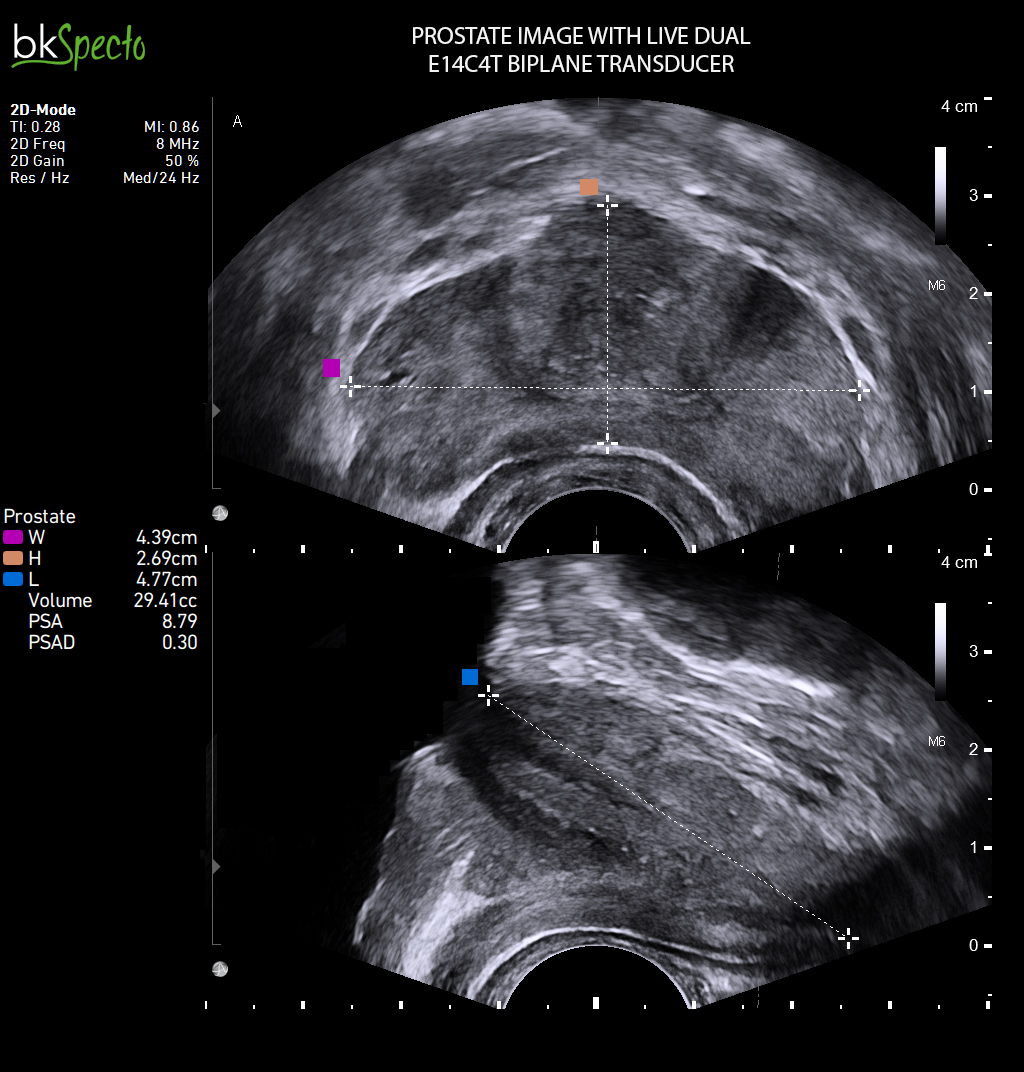

- Modul sinh thiết và điều trị u xơ tiền liệt tuyến (TUR) qua ngả trực tràng dưới dướng dẫn siêu âm _Prostate Imaging & Biopsy: Đặc biệt kỹ thuật điều trị u xơ tiền liệt tuyến bằng hạt phóng xạ (brachytherapy)